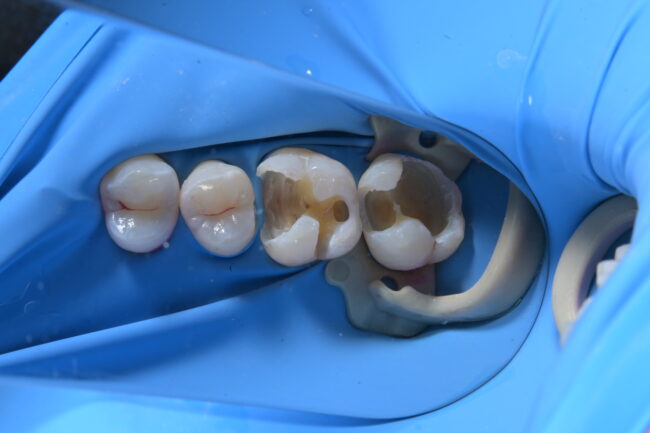

ラバーダムを用いた歯科治療〜宇部市歯医者

歯が欠けた・銀歯が取れた場合にラバーダムを使った歯科治療〜宇部市歯医...

宇部市歯医者 虫歯治療をラバーダム防湿下で行いました。歯の神経を守る...

宇部市歯医者 ラバーダム防湿 セラミック治療 歯の神経を守る

宇部市歯医者ブログ ラバーダム防湿とダイレクトボンディング 白い歯 ...

宇部市歯医者 ラバーダムを使用したダイレクトボンディング 虫歯治療